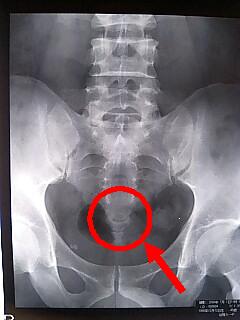

しのさんの

中身です

(笑)

レントゲン写真が

欲しかったので

看護婦さんに

お願いしてみたら

一枚500円で

コピーしてくれるって

言ったんだけど

フランクな先生に

診察室に呼ばれて

お金かかるから

パソコンを携帯で

撮って行けば

いいじゃない

けっこうおっきくて

邪魔になるしねー

撮らせてくれました

キレイにポッキリ

いってますね~

尾てい骨を

ポキッとな

人生初骨折が

尾てい骨て

ウケません

にしても

いてー

安静にします